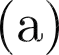

Objective: The objective of this work is to introduce and demonstrate the effectiveness of a novel sensing modality for contact detection between an off-the-shelf aspiration catheter and a thrombus. Methods: A custom robotic actuator with a pressure sensor was used to generate an oscillatory vacuum excitation and sense the pressure inside the extracorporeal portion of the catheter. Vacuum pressure profiles and robotic motion data were used to train a support vector machine (SVM) classification model to detect contact between the aspiration catheter tip and a mock thrombus. Validation consisted of benchtop accuracy verification, as well as user study comparison to the current standard of angiographic presentation. Results: Benchtop accuracy of the sensing modality was shown to be 99.67%. The user study demonstrated statistically significant improvement in identifying catheter-thrombus contact compared to the current standard. The odds ratio of successful detection of clot contact was 2.86 (p=0.03) when using the proposed sensory method compared to without it. Conclusion: The results of this work indicate that the proposed sensing modality can offer intraoperative feedback to interventionalists that can improve their ability to detect contact between the distal tip of a catheter and a thrombus. Significance: By offering a relatively low-cost technology that affords off-the-shelf aspiration catheters as clot-detecting sensors, interventionalists can improve the first-pass effect of the mechanical thrombectomy procedure while reducing procedural times and mental burden.